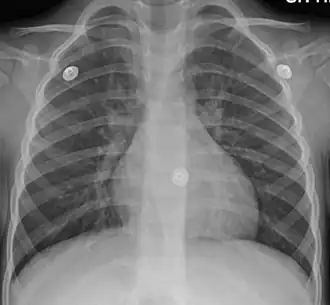

| Figure A shows the location of the lungs and bronchial tubes. Figure B is an enlarged view of a normal bronchial tube. Figure C is an enlarged view of a bronchial tube with bronchitis. | |